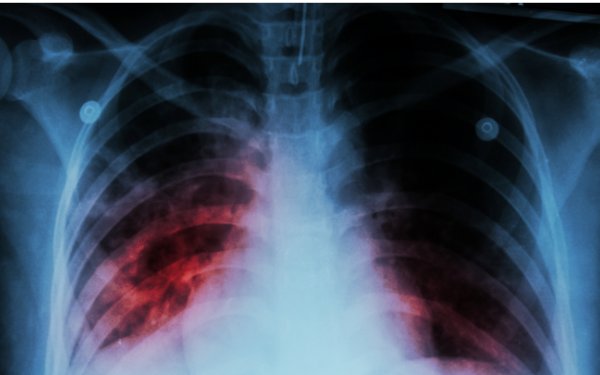

Ötən il 198 uşaq və yeniyetmə vərəmə yoluxub

Ötən il 198 uşaq və yeniyetmə vərəm xəstəliyinə yoluxub.

Bunu Səhiyyə Nazirliyi Elmi Tədqiqat Ağciyər Xəstəlikləri İnstitutunun direktoru İradə Axundova deyib.

O bildirib ki, 2024-cü il üçün bu göstərici 278 olub.

"2015-ci ildə hər 100 min nəfərə düşən vərəmlə xəstələnmə göstəricisi 41,1 olduğu halda, 2025-ci ildə bu rəqəm 21,5-ə enib. Vərəm xəstələrinin təxminən üçdə ikisini kiş...